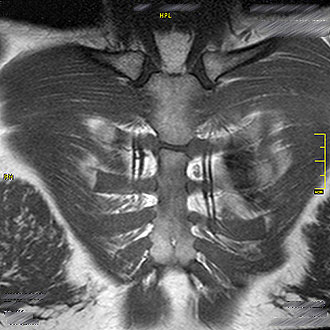

Die MRT des Brustkorbs (Thorax) ermöglicht eine strahlungsfreie Darstellung der Weichteile, Knochen und Gefäße im Brustbereich.

Im Kernspin Zentrum Köln führen wir ausgewählte MRT-Untersuchungen im Brustraum durch – insbesondere zur Beurteilung des Mediastinums und bei speziellen Fragestellungen des Brustkorbs.

Für die Darstellung des Mediastinums (Raum zwischen den Lungenflügeln) ist die MRT besonders geeignet.

Im Kernspin Zentrum Köln lassen sich mit der MRT sowohl das vordere als auch das hintere Mediastinum exakt abbilden.

Die MRT ermöglicht hier eine präzise und strahlungsfreie Diagnostik der Weichteile, Gefäße und angrenzenden Strukturen.

Eine MRT des Brustkorbs kann im Kernspin Zentrum Köln bei speziellen Fragestellungen sinnvoll sein.

Insbesondere die Darstellung des Schlüsselbeins und Brustbeins (Sternum) gelingt mit der MRT sehr gut.

Auch bei entzündlichen Prozessen oder Verletzungen der Brustwand kann die MRT eine wichtige Ergänzung zu anderen Verfahren sein.